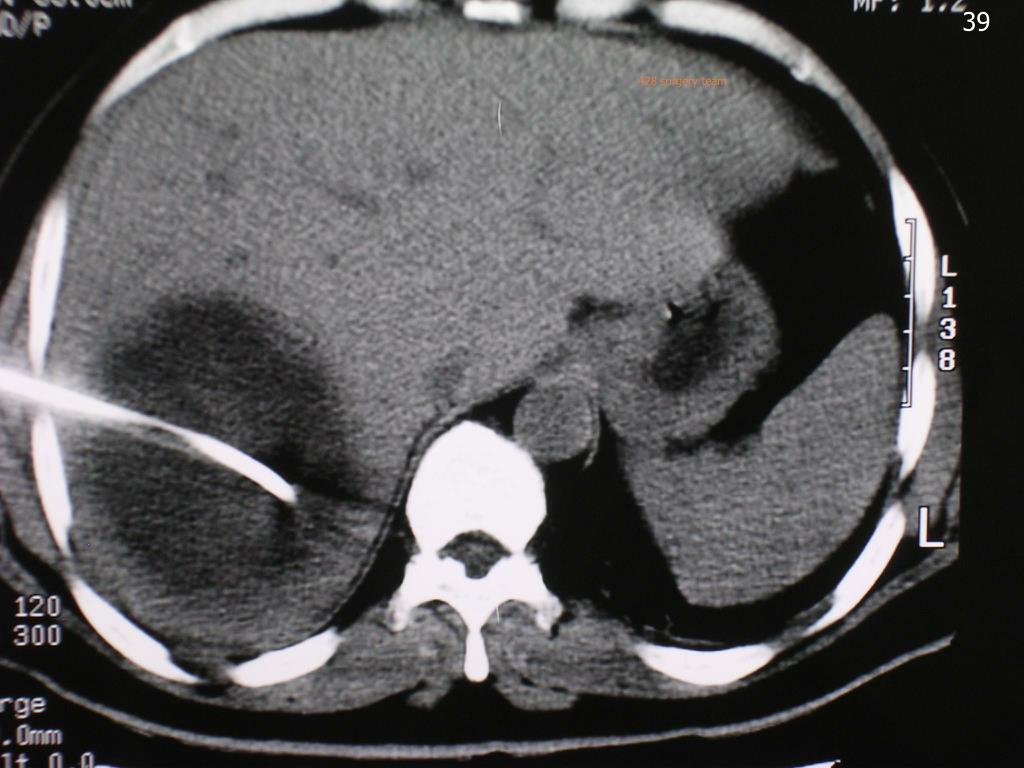

39. 428 surgery team